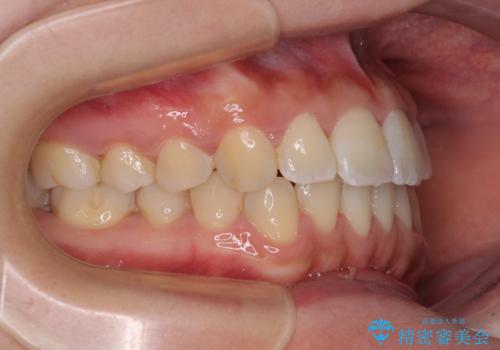

軽微な歯列不正をワイヤー矯正で整える

部分矯正でしたが、咬み合わせに違和感が出ることなく気になる部分を改善させることができました。